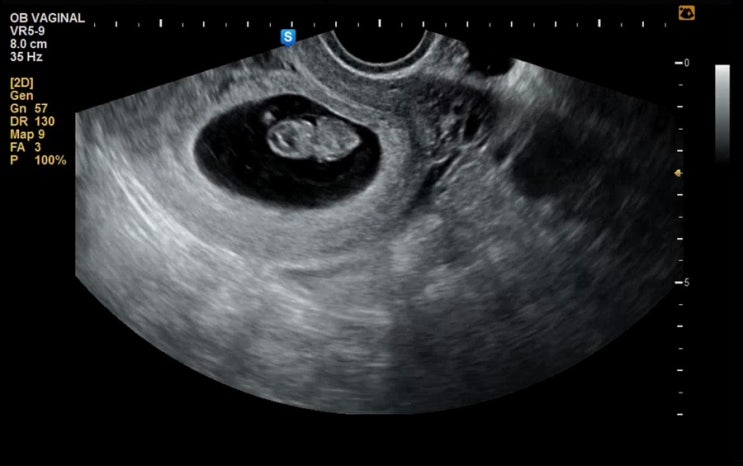

임신일기 (4) 8주차 팔 다리가 생긴 수수 / 입덧 보다는 먹덧?

임신 8주차 일기 / 8w6d 7주차 때 두번째 진료 후 몇일 뒤 살짝 피비침이 있어서 병원에 다녀왔다. 다행히 ...